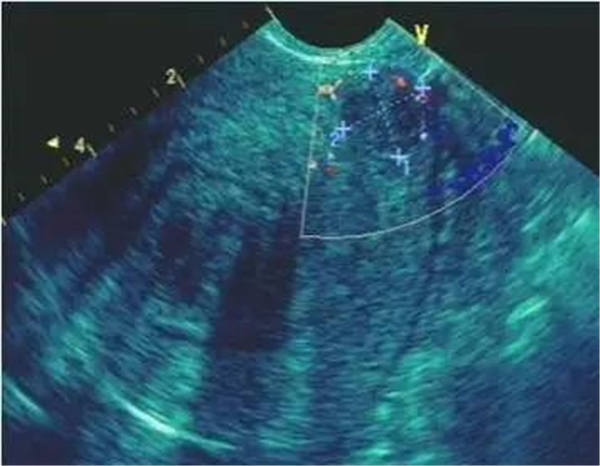

作为最特异的超声心动图特征,当右室/左室前后径比值 > 0.5;右室/左室横径(右房/左房横径)比值 >1.1或者左心室收缩末期和舒张末期径均减小,尤以舒张末期为著时,即可判定血栓性肺栓塞症。

右室壁运动幅度减低

正常情况下,右室前壁运动幅度应>5 mm,右室游离壁运动幅度会>8 mm,但对肺栓塞(PTE)患者,右室壁基底部至游离部运动幅度减低,甚至消失。